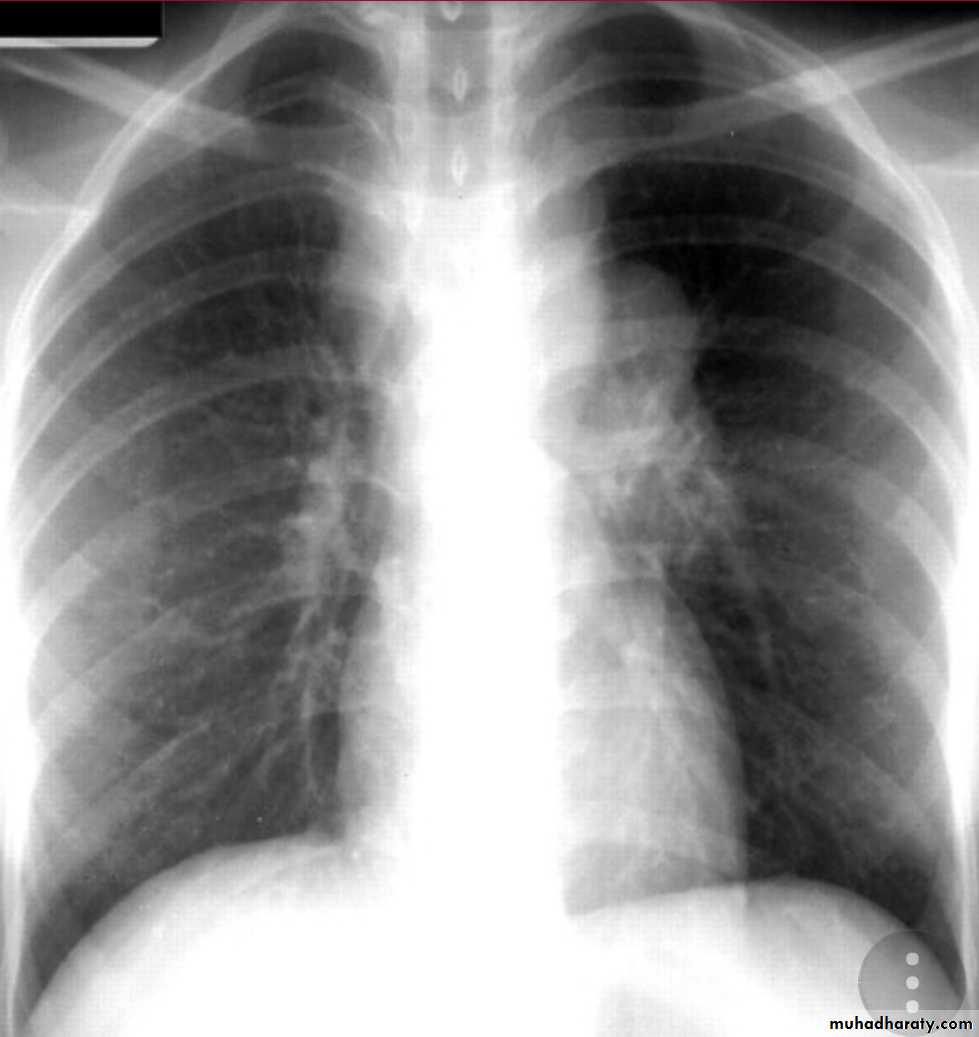

Either occurs as a reinfection by mycobacterium TB or reactivation of primary infection when there is impairment in the immunity of the patient.Grossly: usually occurs at the apex of the lung with minimal lymph node involvement. There is marked damage in the lung parenchyma with cavity formation

Microscopically: Epitheloid granulomas with central necrosis & cavity.

Healing by fibrosis or may spread forming progressive secondary TB

* or enter through bronchial tree leading to tuberculous bronchopneumonia or spread into the pleural cavity leading to pleural effusion.

X- ray,